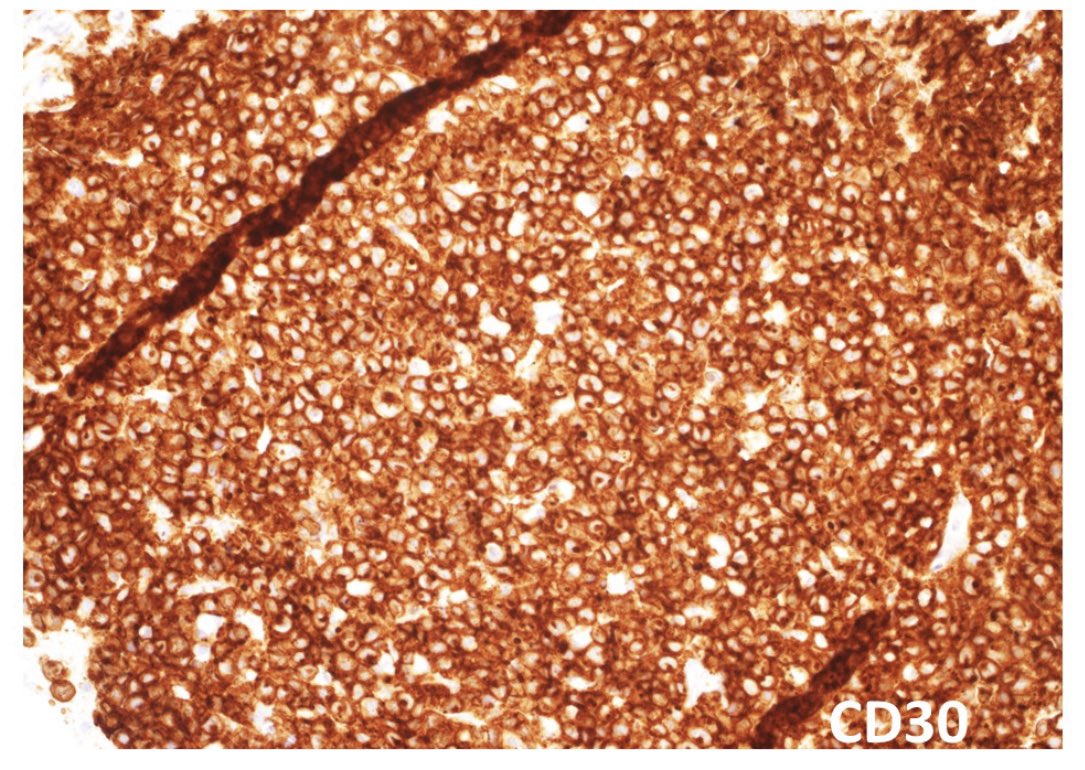

63/male with abdominal lymphadenopathy. DQ gave the initial clue to hemepath diagnosis. Positive CD3/5/7/25. CD30 diffuse, ALK1/CD20 negative. CD30+ Mature T-cell lymphoma. D/D ALCL or ATLL HTLV1 is positive! #cyto #hemepath #PathTwitter Kevin Kuan Yanhua Wang #bridgingcytoheme